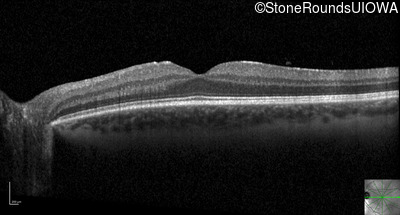

Optical Coherence Tomography - Right - 20/20

Exemplar / OCT Stack

Optical Coherence Tomography - Left - 20/20 -2